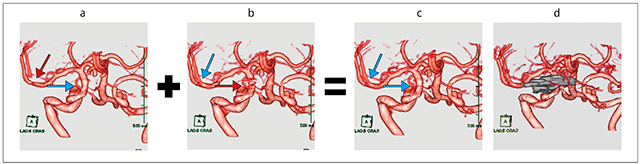

手術ではチタン製クリップを4つ使用したため,手術後の頭部CTにて強い金属アーチファクトを認めた。頭部3D-CTAは金属アーチファクトが強く発生すると予測し,fusionとO-MARを併用した。頭部3D-CTAのFBP VR画像は右内頸動脈の描出は良好であるが,右中大脳動脈が一部欠損している(図5 a)。O-MAR VR画像は,右中大脳動脈の描出は良好であるが,右内頸動脈が描出不良である(図5 b)。fusion VR画像(図5 c)は右中大脳動脈・右内頸動脈とも描出良好であり,手術前の3D-DSA(図4 a)とほぼ同じ血管描出となっているのが確認できる。

図5 症例:未破裂前交通動脈瘤手術後 頭部 3D-CTA(→:描出良好,→:描出不良)

a:FBP VR画像。右中大脳動脈が一部欠損している(↓)。

b:O-MAR VR画像。右内頸動脈が描出不良である(→)。

c:fusion VR画像 クリップなし。右中大脳動脈・右内頸動脈とも手術前の3D-DSAと同様に 描出良好である(→)。

d:fusion VR画像 クリップあり